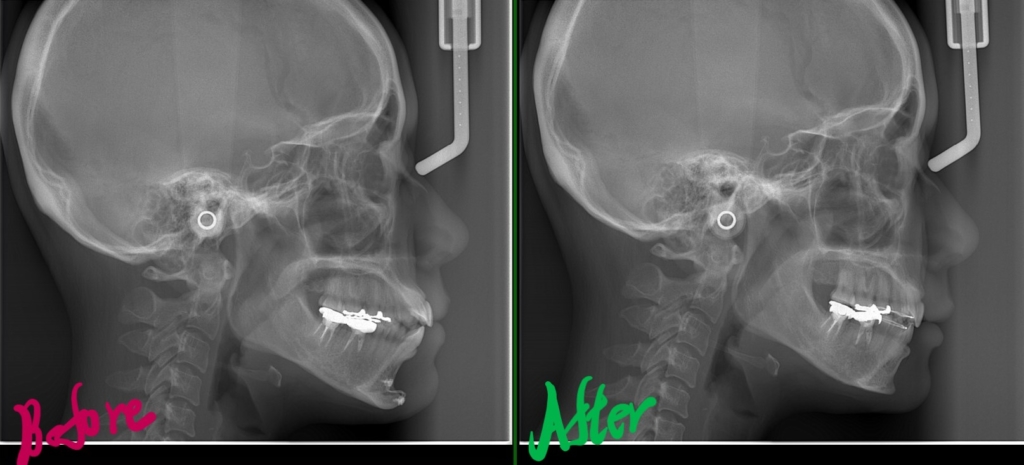

左側が矯正治療前、右側が矯正治療後

レントゲン写真で確認すると、

一応、Eラインが引ける状態です。

矯正後の状態をレントゲン写真で確認すると、

術前も口元にEラインを引くことが出来ました(レントゲン参照)が、お顔全体のバランスという意味で、同じEラインであっても術前と術後ではスッキリ感が異なります。